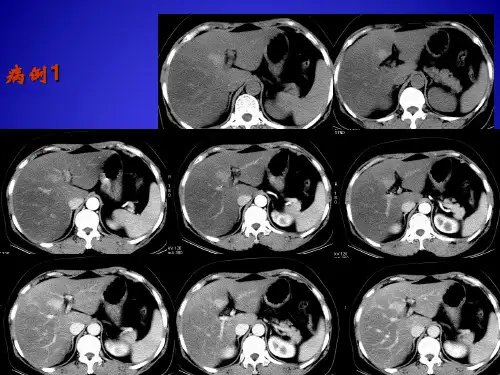

• 胰腺癌为少血管肿瘤、增强扫描时密度 增加不明显,而正常胰腺组织强化明显且 密度均匀,所以增强扫描可以使肿瘤显示 得更清楚.

• 如果肿瘤小于3cm胰腺外形改变不明显时, 增强扫描对显示肿瘤就尤为重要.